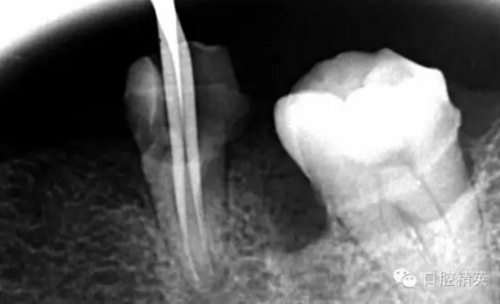

現(xiàn)在開(kāi)始看第二張片子我疏通的遠(yuǎn)舌根,有點(diǎn)問(wèn)題哦!~

7.png

根尖孔偏移,或者是片子角度問(wèn)題,導(dǎo)致我們很難判斷,感覺(jué)像是測(cè)穿。但是我們有根測(cè)儀(前提它是好的),因?yàn)楦鶞y(cè)儀是我們目前對(duì)根管測(cè)量最具有說(shuō)服力,也是最為客觀事實(shí)的。根測(cè)儀沒(méi)有顯示一探入根尖下三分之一顯示“over”的情況(我用的是登士博根測(cè)儀)根管內(nèi)無(wú)滲出,可以測(cè)出根管的長(zhǎng)度。那就證明工作長(zhǎng)度的存在,和可信。在看看正題的近中根的器械,我想問(wèn)問(wèn)大家覺(jué)得是什么器械??